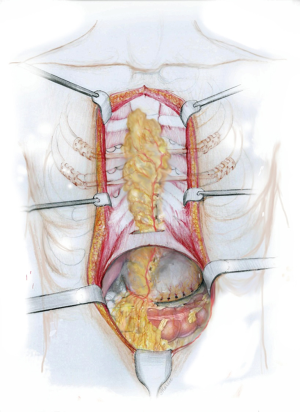

The bone graft could be harvested from the edge of the sternal defect with excising the edge of the sternum with an oscillating saw and bending them into the defect. Additionally, bone chips from the ribs and the xiphoid process should be harvested and placed into the sternal gap. After that the sternum should be reliably fixed with titanium bars (Figure 8). To improve the blood supply an omentoplasty would be an ideal step and for this reason laparotomy and harvesting of the greater omentum based on the right gastro-epiploic arcade is necessary. Harvesting of the greater omentum is performed in the usual fashion creating a flap adequate in size and dividing the vascular tributaries between the right gastro-epiploic arcade and the gastric wall. The harvested flap is transposed in front of the sternum via a window in the anterior portion of the diaphragm to decrease the risk of postoperative incisional hernia (Figure 9). Two vacuum drains should be placed.